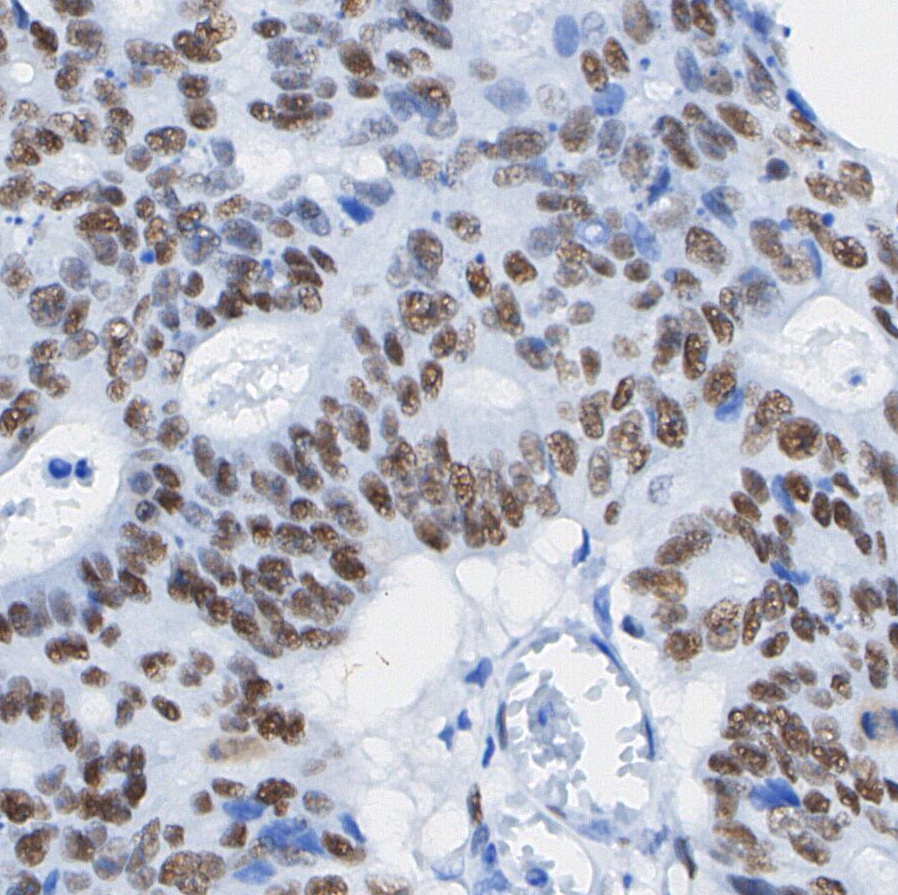

• F0451-IHC1

Immunohistochemical analysis of formalin fixed paraffin embedded human Colorectal cancer tissue with F0451 at 1/200 dilution.